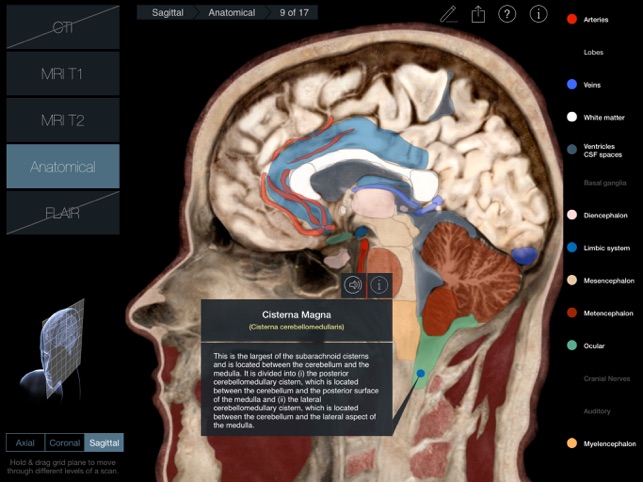

170 images in 3 planes with 2 scan types for each plane (a third for the Axial plane) and anatomical slices for each plane.

•Anatomical (Axial, Coronal and Sagittal slices of the head and brain)

A 3D plane (Axial, Coronal or Sagittal) is pulled or pushed through a 3D head to navigate through the 17 scans in that plane.

300 individual structures labeled along with descriptions and voice over pronunciations.

Individual structures are grouped into 14 categories and each category can be turned on or off to allow for clearer identification of structures.

•Latin nomenclature for each anatomical structure

•Detailed descriptions included